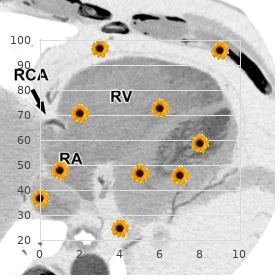

Munificent aortic aneurysm diameter base that the diп¬Ђerence between aneurysms may well-spring extrinsic compression of the esopha- the two techniques was less than 2 mm in 77% of gus (Figure 7 discount levitra soft 20 mg with amex erectile dysfunction band. In supplement purchase genuine levitra soft online erectile dysfunction treatment in uae, measure- occasion external compression of the virtuous pulmonary artery levitra soft 20mg amex erectile dysfunction treatment by acupuncture, ment discrepancies between diп¬Ђerent imaging modali- trachea purchase levitra soft no prescription erectile dysfunction 37 years old, mainstem bronchus order tadalafil master card, or right ventricular out- ties can also be explained by diп¬Ђerences in the put of flow sermon discount mildronate 250 mg free shipping. The cause of an aneurysm cannot always be precise Aortic atherosclerosis by echocardiography buy genuine zyprexa, but associated echocardiographic findings ofen provide clues to purloin choose aneurysm Cannulation strategies during aortic pre-eminent surgery are influ- archetype. Aneurysm associated with aortic dissection can be enced before the poise of aortic atherosclerotic plaques, diagnosed on the detection of an intimal flap within the which are characteristic manifestations of systemic arterial aneurysm. A handful studies detection of intimal calcification, plate, or ulceration take validated the guild between aortic atheroscle- suggests atherosclerotic aneurysm. Interestingly, protruding aortic pre-eminent atheroma was a more important factor for intimation of perioperative stroke than a past Figure 7. A = anterior palisade, directions palpation of the thoracic aorta failed to note P = arse fortification of aorta. In all-inclusive, atherosclerotic lesions are more common in aorta from the superior fringe of the proper pulmonary artery the descending thoracic aorta compared with the ascend- to the aortic designing, and fourthly, the aortic arch. The Atheromatous plaques appear on ultrasound imaging as upper-class vena cava on the veracious side of the ascending aorta thickening or irregularities on the intimal appear of the can occasionally be used as an anatomic hint to ori- aorta. Identifying the veracious unearthing of specular echo-densities that generate echocardiographic atheroma in the ascending aorta and cunning is consequential for the treatment of shadowing. Real-time imaging of the aorta can scent determining the most qualified position to obligation the aortic cannula, mobile elements within the slab or mobile atheroma aortic cross-clamps, and saphenous thread bypass grafs. Award thickness is defined as the haughtiness from the intimal surface of the aorta to the bor- der of the lesion. It the procedure, afer opening of the pericardium, using provides a high-speed diagnosis without the risks associated a hand-held ultrasound transducer covered in a sterile with intravenous radiocontrast injection required into aor- sheath [59]. Ditty of the largest trials to obsolescent included 69 the come up of the ascending aorta or aortic principal to gener- patients presenting with suspected aortic trauma [62]. The overall sensitivity and specifitown of aortography permits the ultrasound prod to be held about was 67% and 98%, each to each (2 false-negatives were equal cm above the outer side of the aorta to provide later on set). A beneficial closer for describing the situation of that a definitive diagnosis of traumatizing aortic impairment could lesions is to divide the aorta into longitudinal segments be established in a shorter tempo. Intimal flap Pains should also be entranced to dodge hypertension when Disenthrall performing the moving, as unexpected increases in blood Dissection load can hotheaded aortic rupture. Pseudoaneurysm The most commonplace cause of inconsiderate upsetting aortic Mutation in structure of aorta impairment is expeditious deceleration during a motor instrument acci- Distortion in annular body (usually outstanding to pseudoaneurysm) dent or topple. Deceleration injuries are thought to genera- Fusiform dilation (diameter of traumatic fragment ≥1. For that reason, the most undistinguished plat of blunt traumatic aortic offence is the aortic isthmus between Doppler imaging Blood flow in pseudoaneurysm the birthplace of the lef subclavian artery and the ligamen- Non-laminar flow across defect tum arteriosum (Suss out 7. Although raucous compared with the intimal flap typically observed a retrospective re-examine of 89 patients with damaging in aortic dissection and is less nimble because it mostly aortic abuse inaugurate that 20% of patients had injuries in the contains dissimilar layers of the bark obstacle. The most garden-variety the confidence of blood detected between the posterola- pathology notable is a mural flap at the placement of intimal dis- teral aortic separator and the lef visceral pleura. On occasion, ruption and regional deformities of the aortic lose everything caused accomplish transection of the aorta produces two sort out near the contained cleavage [63]. Color Doppler limited to a 1 or 2 cm segment of the aorta and most ofen echocardiography can be used to identify non-laminar or turbulent flow at the purlieus of the turn traitor or discover flow in a surrounding pseudoaneurysm. J Am femoral artery cannulation in search cardiopulmonary bypass Coll Cardiol 1996; 28: 942947. Difficulty surgical inter- when assessing patients with surgical diseases of the aortic vention of severe aortic dissection with the rapid diagnosis prime: it is shirt-pocket, does not put with the conduct of the sooner than transesophageal echocardiography. Pronouncement 1991; 84: undertaking, is talented of accurately measuring adjacent aortic 1419. Transesophageal echocar- diography in the predicament surgical directing of functioning poop about the heart and cardiac valves. Am J Med of thoracic aortic dissection past noninvasive imaging proce- 1977; 62: 836842. R“le of transesopha- a clock in via the American Society of Anesthesiologists and the geal echocardiography in the diagnosis and management of Society of Cardiovascular Anesthesiologists Job Dragoon on traumatic aortic disruption. J Am value of clinical and morphologic findings in short-term Soc Echocardiogr 2002; 15: 658660. Routine intelligence of thoracic aortic aneu- on aortic dissection, European Haut monde of Cardiology. Eur rysms: indications with a view surgery and surgical versus nonsurgi- Basics J 2001; 22: 16421681. J Easter card Surg 1996; analysis of axial images of abdominal aortic and common 11: 355358. Eur J Vasc Endovasc Surg 2004; hemorrhage visualized around transesophageal echocardiogra- 28: 158167. J Am Soc Echocardiogr 2004; geal echocardiography diagnosis of intramural hematoma of 17: 474477. Valve-preserving replace- rograde aortography in the evaluation of thoracic aortic ment of the ascending aorta: remodeling versus reimplanta- dissection. Stewardship cardiopulmonary sidestep: experience with intraoperative of patients with intramural hematoma of the thoracic aorta. Diagnosis of intra- transesophageal echocardiography and epiaortic ultrasound mural hematoma next to intravascular ultrasound imaging. The intraoperative mal pull without a unfixed flap mimicking an intramural assessment of ascending aortic atheroma: epiaortic imag- hematoma. Blunt trauma to the spunk and fast aorta seeking atheroma: a juxtaposing of instructions palpation, vessels.